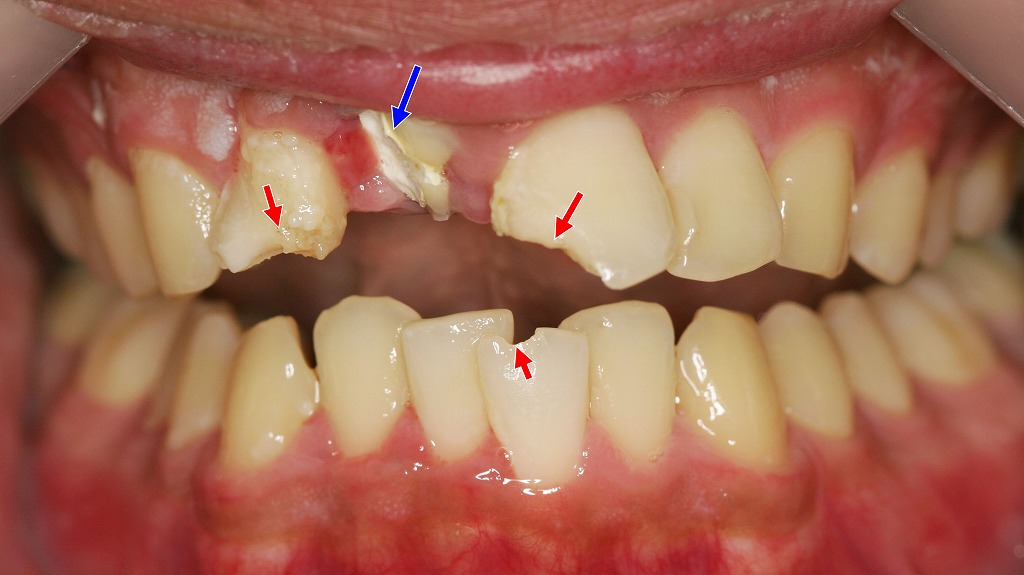

転倒などの外傷により前歯を強く打撲した症例。赤矢印部は歯冠破折に対してコンポジットレジン充填で対応可能な部位を示します。青矢印部は歯髄損傷を伴い、根管治療後に補綴処置が必要となった歯です。歯の外傷では、見た目の破折が軽度でも歯髄壊死や根尖病変を生じることがあり、長期的な経過観察と適切な治療介入が重要となります。